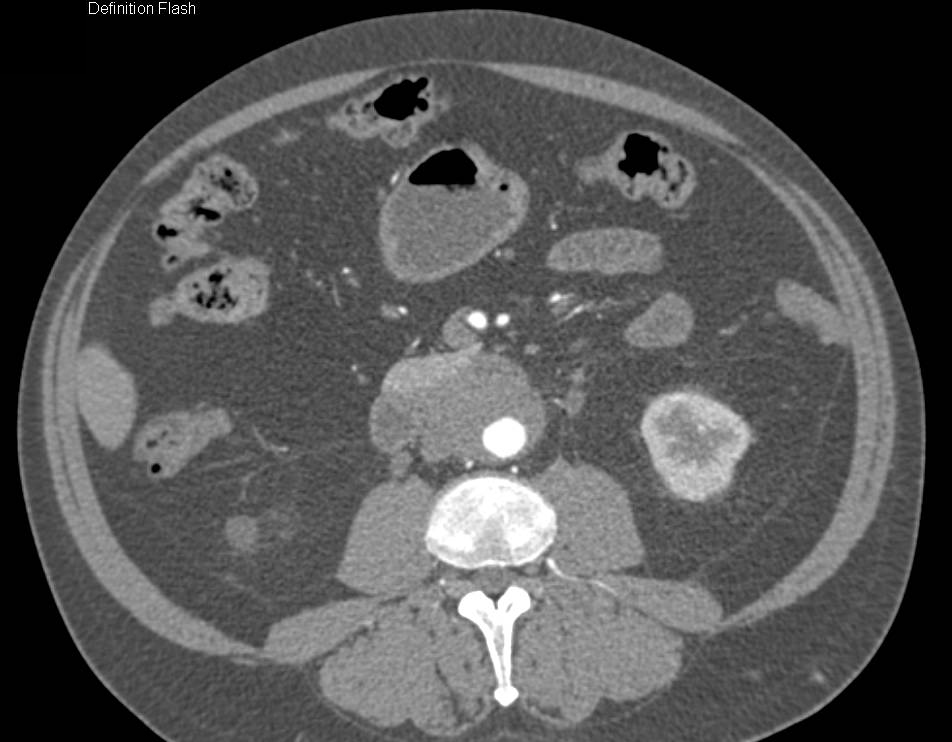

Focal Crohn's Disease and Bladder "Jets"